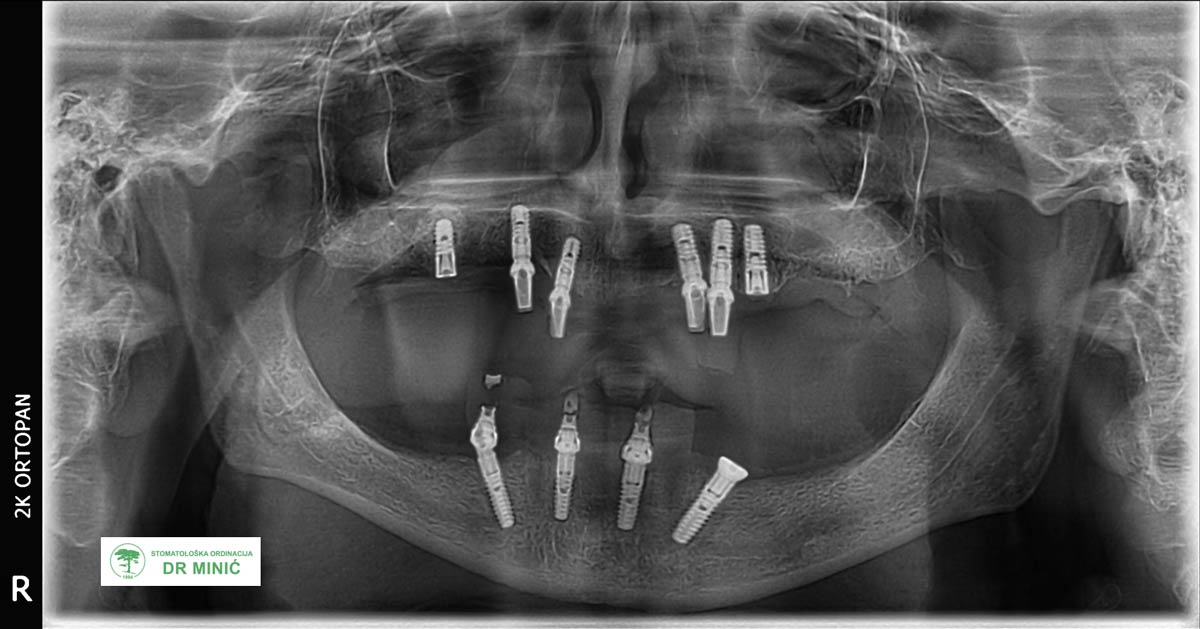

Ova studija slučaja prikazuje terapiju All-on-4 i All-on-6 metodom kod pacijenta sa izraženim gubitkom zuba u obe vilice. Terapija je izvedena u stomatološkoj ordinaciji dr Minić u Beogradu uz primenu savremenih implant sistema i individualnog plana rehabilitacije.

Klinička dijagnoza

Pacijent ima 70 godina. U gornjoj vilici je ranije rađen metalokeramički most, a u donjoj vilici nedostaje više zuba. Zbog ranijeg gubitka kosti i problema sa desnima (upalom oko implanata), stanje u ustima je bilo složeno i zahtevalo je opsežniju terapiju.

Na desnoj strani gornje vilice urađen je nadogradnja kosti (tzv. sinus lift), kako bi se stvorili uslovi za ugradnju implanata. Nakon toga ugrađeno je šest Bredent implanata u gornju i četiri u donju vilicu.